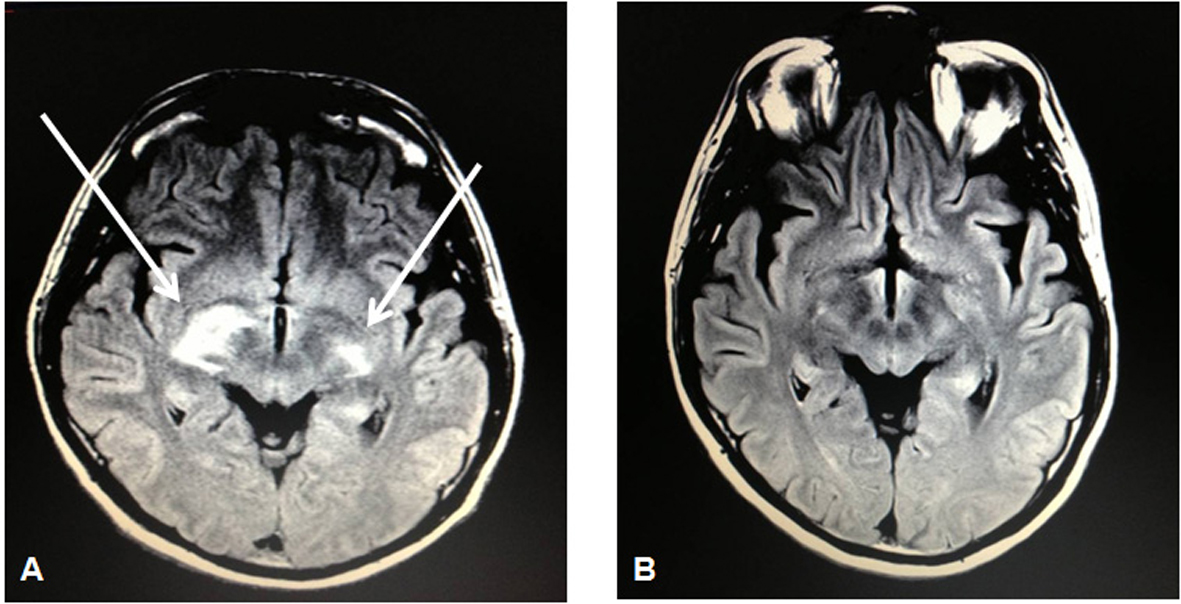

Laboratories were notable for an absolute CD4 count of 23 CMM and HIV viral load of 76,000 copies/mL despite having been on antiretroviral therapy since his HIV diagnosis 4 years earlier. Subcutaneous tissue biopsy of the left triceps showed clusters of large malignant lymphoid cells with staining characteristics consistent with PTCL as before. A repeat staging CT scan showed a 3.4 × 2.1 cm L5-level mass posterior to the right psoas. An MRI of the brain would show bilateral signal enhancement within the lateral subthalamus, midbrain, and internal capsule (Fig. 2). CSF analysis would show the presence of atypical lymphoid cells suspicious for lymphoma. Bone marrow biopsy, however, would show an absence of involvement by lymphoma.

![]() Click for large image | Figure 2. MRI brain showing bilateral signal enhancement (more on the right than left side) within the lateral subthalamus, midbrain, and internal capsule (A) followed by resolution of such lesions on a repeat MRI brain 5 months later (B) after 3 cycles of intravenous pemetrexed 900 mg/m2. |

The patient subsequently received high-dose intravenous (IV) methotrexate (8 g/m2) for his relapsed peripheral T-cell lymphoma (stage IV) that originally manifested as a gastric mass. Due to extremely poor elimination following the methotrexate administration, he would instead complete 3 cycles of IV pemetrexed 900 mg/m2 (in 3-week cycles) that was well tolerated as he experienced only a grade I nausea as an adverse event. Subsequent restaging PET-CT and MRI of the brain would show a complete radiographic response (Fig. 2). At the time of this report, he is scheduled to undergo autologous stem cell transplantation in the setting of his second complete remission.